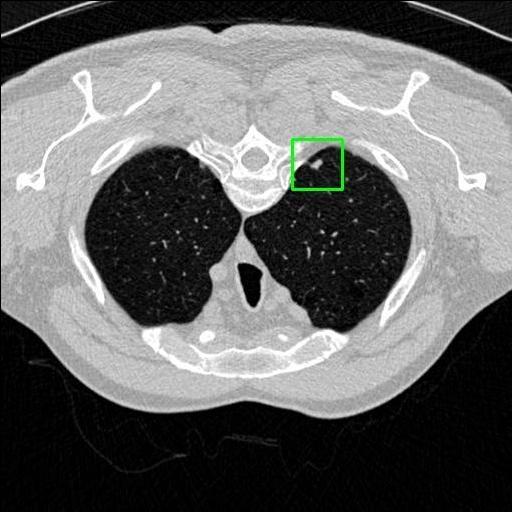

We developed an AI-based system using deep learning models for analyzing lung CT scans to detect and classify pulmonary nodules. We chose the YOLOv11 architecture for its enhanced object detection capability and adapted it specifically for medical imaging, incorporating pixel-level precision and severity classification.

Classification into three severity levels with colored bounding boxes.

Successfully built and deployed an AI model (YOLOv11) capable of detecting lung nodules in CT scans with high accuracy and real-time performance.

Designed a severity classification system that categorizes nodules into null, moderate, and severe using colored bounding boxes, assisting in rapid clinical decision-making.